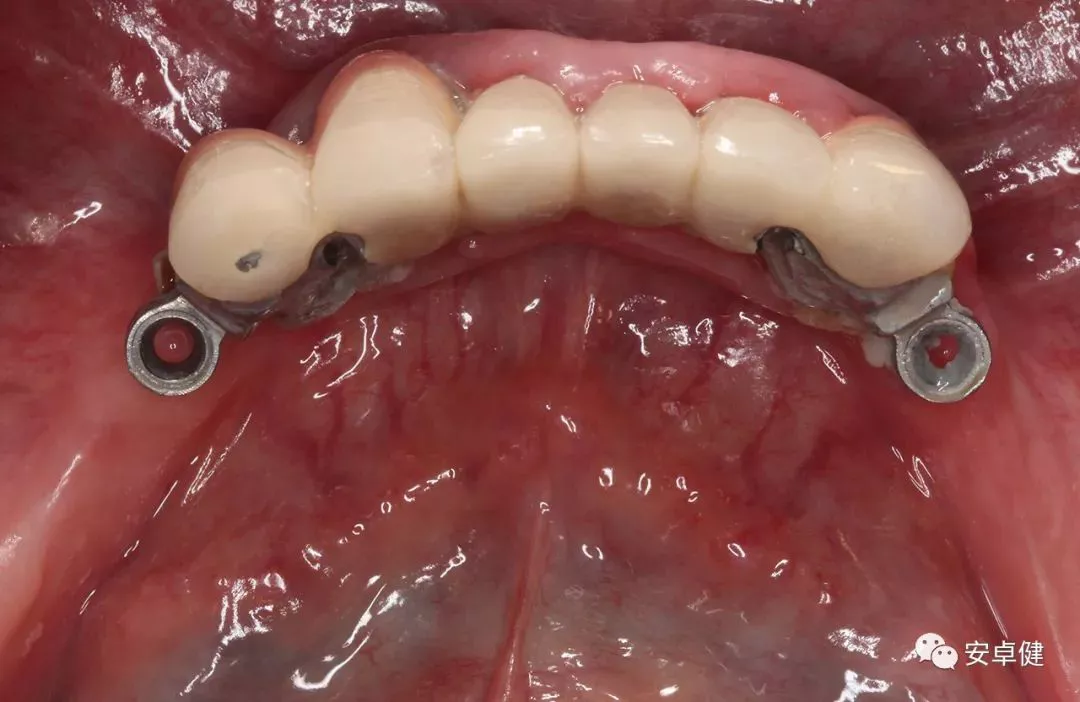

最终修复体合面照

最终修复体正面照

最终修复体正面咬合照

最终修复体侧面咬合照

最终修复复诊合面观

戴最终修复体合面观

▷ 永久修复

患者术后16个月:

• 于口内试戴原厂纯钛切削一体式桥架,并检查前牙排蜡外形及后牙咬合关系;

• 聚合瓷烤塑制作最终修复体;

• 为减少牙面磨耗,于后牙区制作360度防裂纯钛金属带;